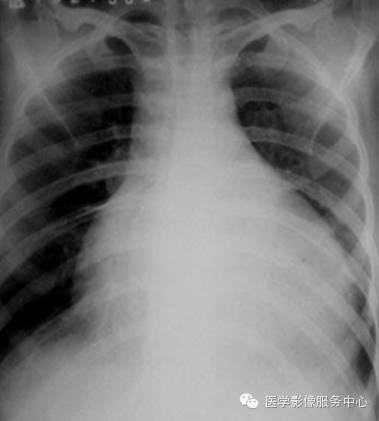

X线检查对少量的心包积液的诊断有限度。当积液量增加时,可见心影向两侧增大,其至呈球形,心缘搏动普遍减弱或消大;部分患者可伴有上腔静脉扩张。

CT表现为:包腔增宽,心包腔内液体呈水样密度。CT值介于12HU~40HU之间,血性及渗出液CT值较漏出液及乳糜液CT值较低。少量积液仰卧位主要集中在左室背侧,中量积液对扩展至心脏腹侧,大量积液时可包裹所会心脏及大血管根部,下界可达BNJ水平,心包壁层、脏层间距明显增宽。

一般将心包积液分为三度,

I度为少量积液.积液量小于100ml,舒张期心包脏、壁层间距5mm~15mm;

II度为中等量积液,积液量100ml~500ml。心包脏、壁层间距15mm~25mm;

III度为大量积液,积液量>500ml,心包脏、壁层间距>25mm。